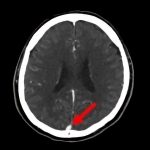

断層撮影

手術前2